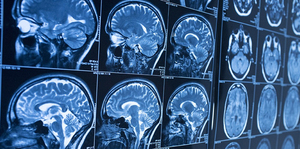

- Differentiate between different radiological modalities.